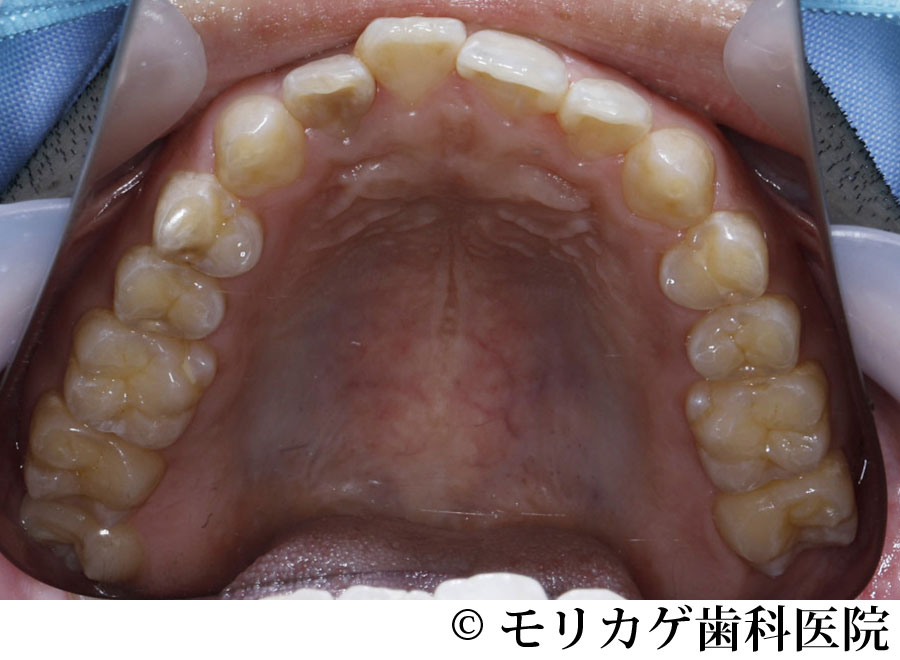

【症例1】マウスピース矯正器具を用いた矯正治療

- 治療前

- 治療中

- 治療後

- 治療名

- マウスピース矯正器具を用いた矯正治療

- 費用

- 1,155,000円(税込)

- 費用内訳

- 診断料:55,000円(税込)

治療費:1,100,000円(税込) - 期間

- 48ヶ月(4年)

※矯正治療:3年+ミッドラインの調整:1年 - 通院頻度

- 1ヶ月に1〜2回

治療内容

患者様の症状

目立たないように矯正をして歯並びを綺麗にしたい。

なるべく痛くないように矯正治療をしたい。 -

治療法

マウスピース矯正装置を採用して審美的な矯正治療をした。

治療結果

実際の治療期間は3年だが、患者様が納得するミッドラインに合わせる為に1年ほど延長しトータル4年かかった。

上顎のミッドラインと下顎のミッドラインがちがうため、上下のミッドラインを合わせる為に時間をいただいた。

現状は噛み合わせも問題なく治療結果に納得していただいている。

※治療結果は患者様によって個人差があります。

治療を行う上での 注意点 (リスク・副作用)

歯牙の転位や捻転の程度によって部分的にブラケットを用いたワイヤー矯正を併用することによって審美性の獲得をする場合がある。